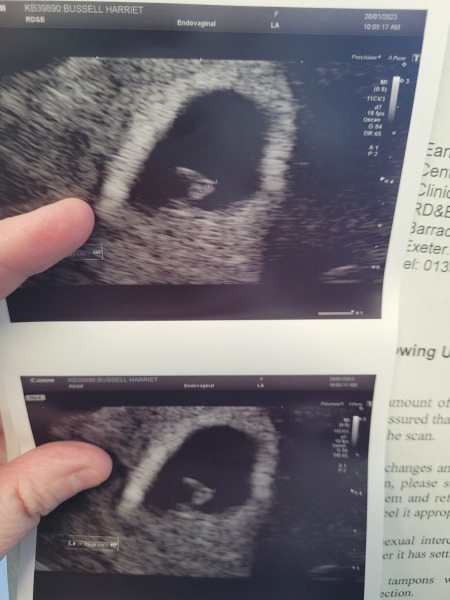

Due to an ectopic pregnancy 2 years ago I've already been in for 2 early scans. The first was too early and nothing could be seen so they couldn't rule out another ectopic, but I had a second scan today and I saw the foetus and the heartbeat! 💗💗💗💗

Your scan pictures are great 😍😍

Got to see our little bean today! Thought I was 7 wks exactly but measured me at 6 wks 4 days. Relieved is not the word since last September we went to the same scan to find only an empty sac… Me & hubby burst into tears as soon as we heard the heartbeat, can relax a bit more now!

@Pebblessss I had the same thing at my first early scan at 6 weeks. We could only see the sac and nothing else. BUT when we went back for the 2nd scan at 7 weeks, we could see the heartbeat. Try not to worry, the sonographer told me it was very normal to not see anything at that stage. Sending positive vibes to you 💗